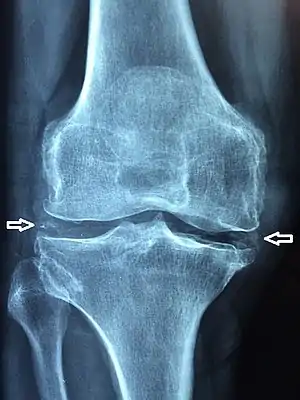

| X-ray of a knee with chondrocalcinosis | |

Chondrocalcinosis or cartilage calcification is calcification (accumulation of calcium salts) in hyaline cartilage and/or fibrocartilage.[1] It can be seen on radiography.

Chondrocalcinosis can be visualized on projectional radiography, CT scan, MRI, US, and nuclear medicine.[1] CT scans and MRIs show calcific masses (usually within the ligamentum flavum or joint capsule), however radiography is more successful.[1] At ultrasound, chondrocalcinosis may be depicted as echogenic foci with no acoustic shadow within the hyaline cartilage.[7] As with most conditions, chondrocalcinosis can present with similarity to other diseases such as ankylosing spondylitis and gout.[1]